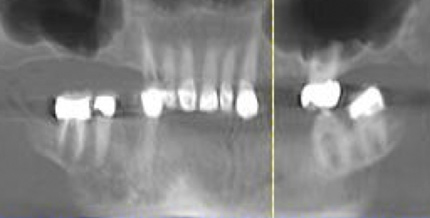

Fig 15. This all-resin interim restoration, which served as a fixed long-term provisional for more than 5 years, is an example of an entry-level option that offers the physiologic benefits of a long-term fixed restoration but with an economic equivalence to a mandibular two-implant overdenture.

Figure 15

Fig 16. This all-resin interim restoration, which served as a fixed long-term provisional for more than 5 years, is an example of an entry-level option that offers the physiologic benefits of a long-term fixed restoration but with an economic equivalence to a mandibular two-implant overdenture.

Figure 16

Fig 17. A three-implant fixed bridge may be an immediate-load alternative for a fixed restoration as opposed to a two-implant overdenture. In addition to significant cost reduction due to pre-manufactured components, the final long-term restoration is delivered on the day of surgery.

Figure 17

Fig 18. A three-implant fixed bridge may be an immediate-load alternative for a fixed restoration as opposed to a two-implant overdenture. In addition to significant cost reduction due to pre-manufactured components, the final long-term restoration is delivered on the day of surgery.

Figure 18